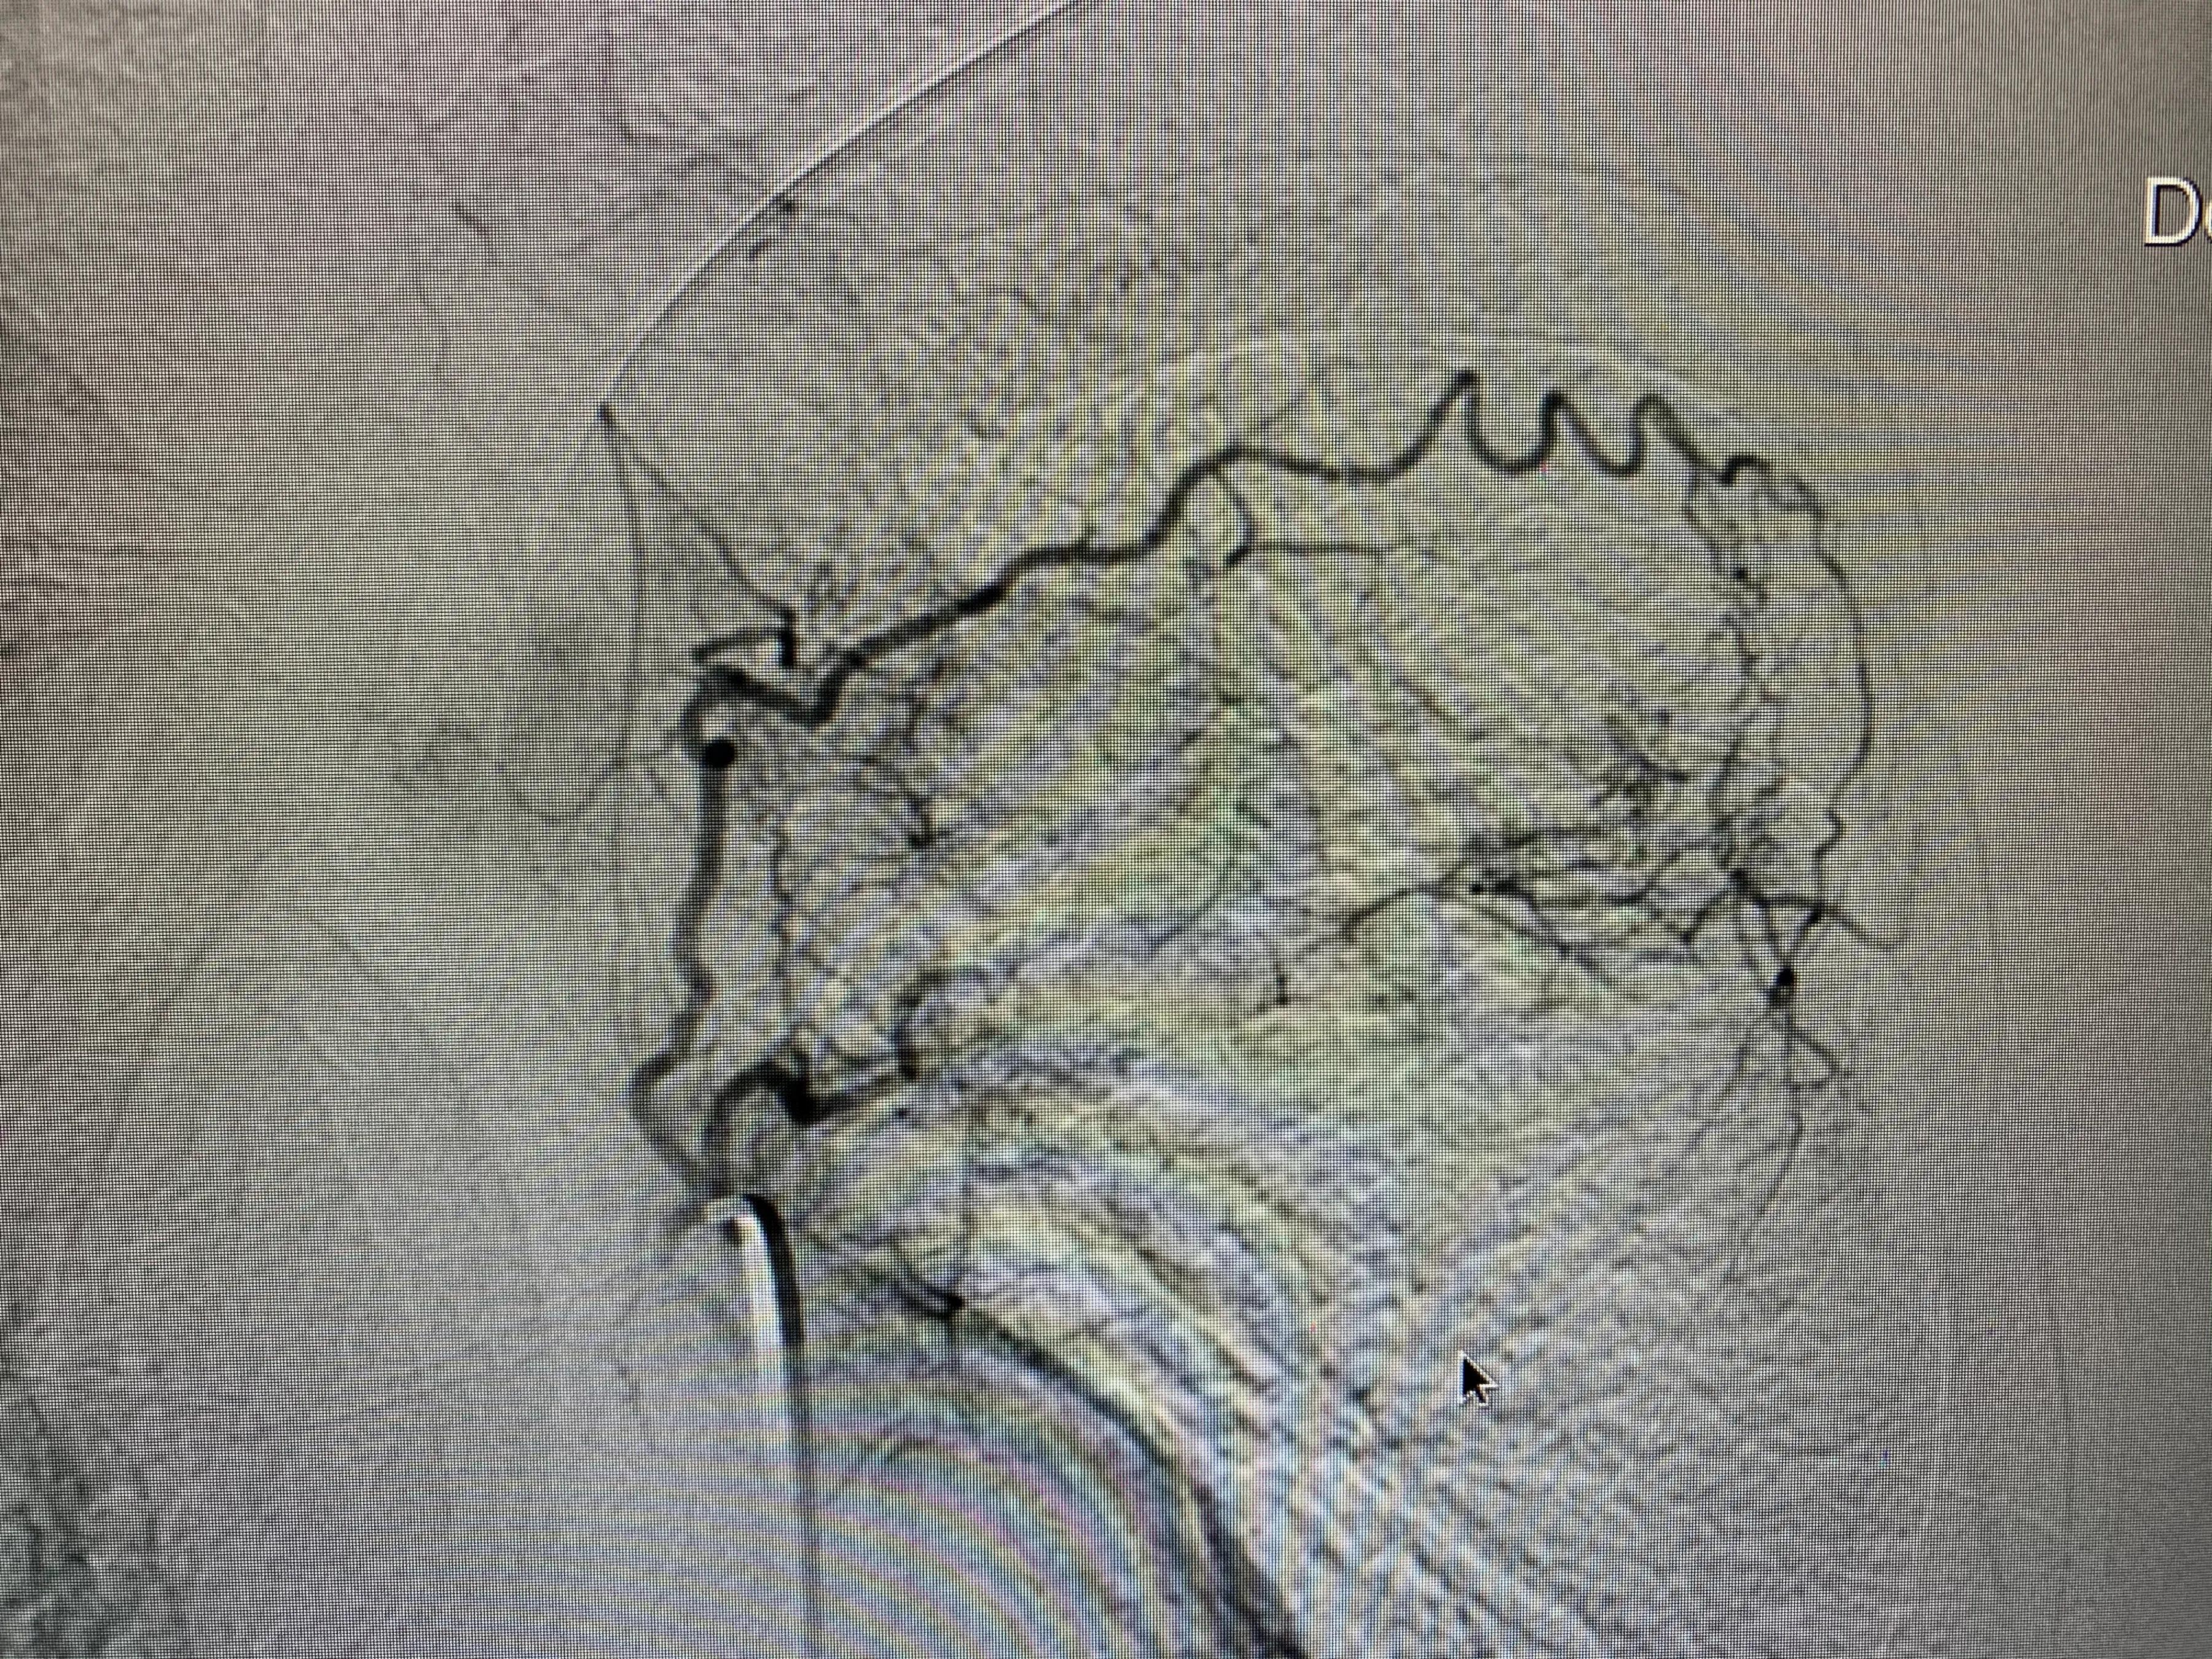

老年男性患者,左肺腺癌,化疗期间出现了咯血,术中可见左侧支气管动脉、左侧多支肋间动脉及左侧胸阔内动脉均参与肿瘤的血供,并可见以上动脉-肺动脉瘘,经肿瘤供血动脉灌注化疗药并且进行栓塞,术后未再出现咯血,一个月复查ct提示肿瘤较前明显减小,阻塞症状较前缓解。微创介入即经导管灌注化疗栓塞治疗肺肿瘤能够有效治疗肿瘤并且缓解肿瘤引起的一系列并发症,如咯血、阻塞性肺炎等,当然,肿瘤的治疗是综合治疗,需要多学科的共同参与。